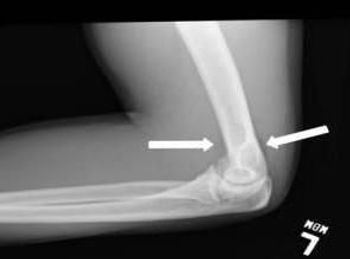

The 27-year-old patient sustained a FOOSH (fall on outstretched hand) injury while roller skating. What classic imaging sign appears on the radiograph of his injured left elbow?